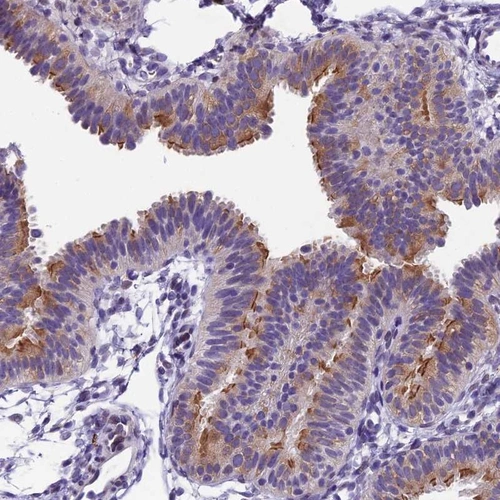

Immunohistochemical staining of human fallopian tube shows distinct positivity in ciliary rootlets.